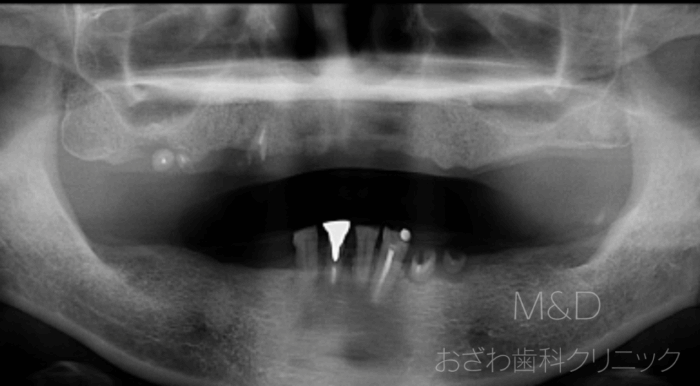

術前

主訴:入れ歯がぐらぐらして痛く、噛めない

上下顎残存歯の抜歯、上顎6本、下顎4本(オールオン4)インプラント